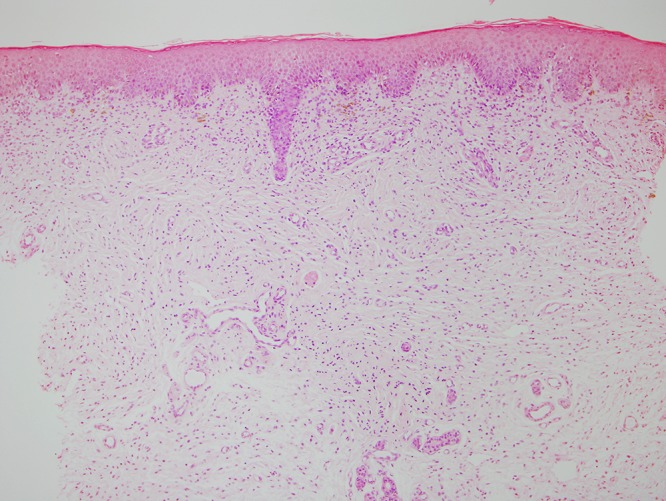

Punch biopsy of the soft plaque on the lower back revealed a proliferation of spindle cells in the dermis, arranged in fascicles. The majority of fascicles were wavy and surrounded by stroma consisting of thin, delicate connective tissue fibers (Figure 2A). Cells throughout the dermis stained positive for S-100 (Figure 2B) and negative for MelanA (not shown), compatible with the diagnosis of a neurofibroma.

Figure 2.

(A) H&E stained tissue section from SNF lesion on the lower back at 10× magnification, showing proliferation of spindle cells in the dermis, arranged in fascicles. The majority of fascicles are wavy and surrounded by stroma consisting of thin, delicate connective tissue fibers. (B) S100 stained tissue section from SNF lesion on the lower back at 10× magnification, with cells throughout the dermis staining positive for S100. [Copyright: ©2015 Helfand et al.]